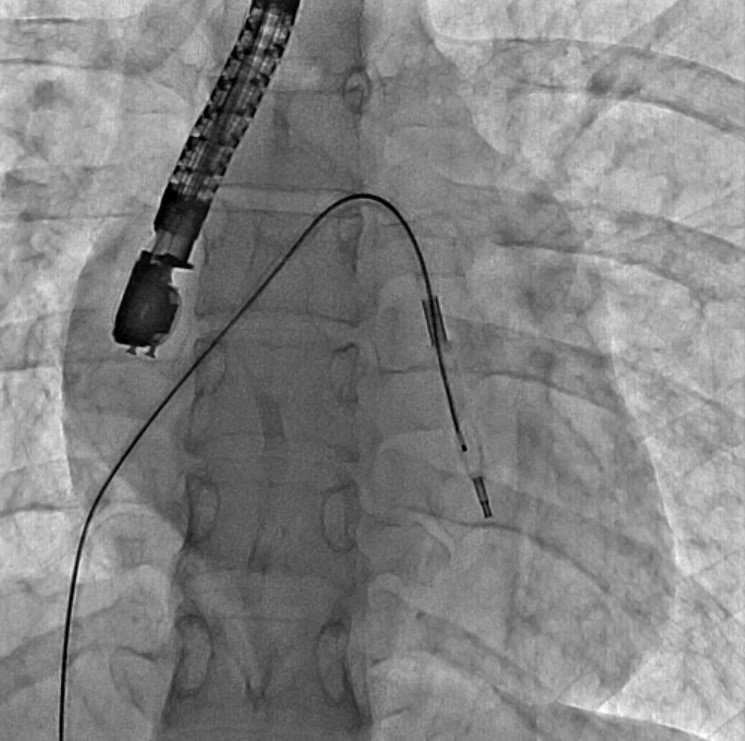

Mitral Balon Operasyonu Adım Adım Kaydedildi

Eskişehir Şehir Hastanesi'nde ilk defa mitral balon operasyonu yapıldı. Operasyon, anjiyografi cihazı ile adım adım kaydedildi.

Eskişehir Şehir Hastanesi'nde ilk defa mitral balon operasyonu yapıldı. Operasyon, anjiyografi cihazı ile adım adım kaydedildi.

Eskişehir Şehir Hastanesi'nde Kardiyoloji Uzmanı Dr. Mehmet Özgeyik ve 4 kişilik ekibi tarafından ilk defa mitral balon operasyonu yapıldı. Türkiye'de az sayıda yapılan kalp kapağı balon işlemiyle yeni anne olmuş genç bir hasta sağlığına kavuştu. Bu sayede hastalar ameliyat olmaktan, ömür boyu kan sulandırıcı ilaçlar kullanmaktan ve metal bir kalp kapağı ile yaşamaktan kurtuluyor.

Gerçekleşen başarılı operasyon hakkında konuşan Kardiyoloji Uzmanı Dr. Mehmet Özgeyik, "Bu işlemi genellikle kalp kapaklarında ciddi darlık olan genç hastaların kişilere uyguluyoruz. Buradaki amacımız ameliyat olmadan, kasıktan küçük iki damar yolu açarak hastalarımızın kapak darlıklarını uzun süreli olarak genişletmeyi hedefliyoruz. Burada 23 yaşında yeni anne olmuş genç bir hastamıza müdahale yaptık. Hastamız ya kapak ameliyatı olacaktı ya da bu işlem sayesinde kapak darlığını aşmayı planlıyorduk. İşlem gayet başarılı oldu. Hastamızın kapak darlığını genişlettik. En azından 10-15 sene boyunca ameliyata gerek kalmadan hastamızı ilaç tedavisiyle takip etmeyi planlıyoruz" diye konuştu.

Cerrahi operasyonlar yerine mitral balon işlemiyle hastaları sağlıklarına kavuşturmak istediklerini aktaran Dr. Özgeyik, "Hastanemizde ilk kez yapılan bir işlem. Bu işlem için uygun hasta bulmak biraz zor oluyor çünkü çok sık yapılan bir işlem değil. Fakat gelecekte hasta portföyümüzün de artması ile birlikte daha sık yapmayı planlıyoruz. En azından hastalarımızı büyük bir cerrahi operasyona vermeden böyle küçük işlemlerle hayat kalitelerini artırmayı planlıyoruz. Hastamız ameliyata gitmiş olsaydı büyük bir operasyon geçirmiş olacaktı. Göğüs bölgesinde büyük bir kesiğe maruz kalacaktı. Aynı zamanda ömür boyu kullanması gereken farklı ilaçlar olacaktı. Hasta kendisine ait olmayan metal bir kapakla yaşamak zorunda kalacaktı. Biz bu işlemde hastaya kasıktan iki tane damar yolu açtık. Hastaya neşter ile kesme işlemi uygulamaktan kurtardık. Ayrıca hastanın hayatı boyunca kullanacağı kan sulandırıcı ilaçları uzunca bir süre ertelemiş olduk. En önemlisi de hastanın kendi kalp kapağını kullanmasını sağlamış olduk ve metal kapak yükünden kurtulmuş oldu" şeklinde konuştu.